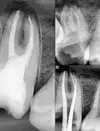

Diş Ağrısı

Diş Çürükleri